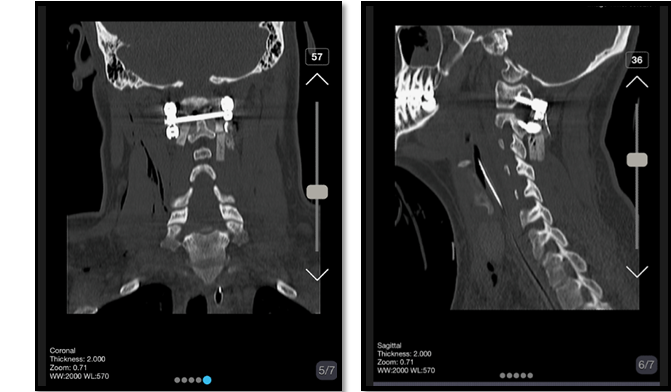

The patient was discharged with a cervical collar after three days. He returned for a follow-up visit after one week, during which we conducted a cervical CT scan (Figure-6). In the CT scan, the impactor showed to be placed appropriately, no sign of displacement was evident. At this point, tracheostomy was removed, the patient reported significant improvement and no longer experienced cervical pain.

Figure 5. post-operative CT images show Lateral mass screw was applied for C1, and a pedicular measuring 24*8 mm in the right part of C2 and 26*4 mm in the left one were used. The fusion was applied to reduce ligament injuries

Figure 6. Cervical CT images after 1 week of surgery. The impactor showed to be placed appropriately, no sign of displacement was evident.